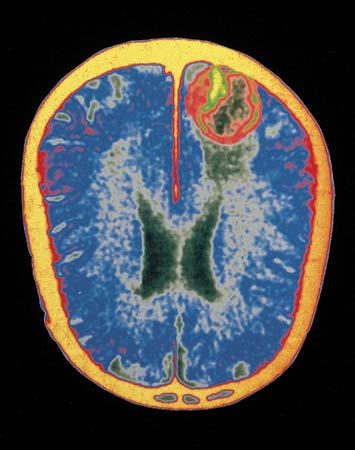

•Brain tumors (SV-40)

The pertussis vaccine is very neurotoxic and is used in the laboratory to produce brain lesions in lab animals for study. But if our child develops brain problems after a DPT vaccination, our doctor will tell us it is coincidence or genetic. Vaccinations have been known to increase the demyelination, a process related to many neurologic diseases and MS is a demyelination disease. Myelin is designed to protect the outer coating of neurons, much like the plastic outer coating over an electrical wire. When this myelin is damaged, neurological disorders, such as, MS, paralysis, or ALS, will result. (Singh mentioned autism as a result of demyelin-ation disorder.) The nerves are short-circuited and do not function normally.

The encephalitis from vaccinations is much more prevalent than we would like to realize, since all vaccines are neurotoxic to begin with. That one child develops encephalopathies from a vaccine and another remains ‘normal’ is not the issue. All children are affected, but some are affected more than others. For example, if a child develops uncontrolled high pitched crying after a vaccine is given, that is written off as a normal reaction and is even listed in medical texts as such. However, if that same child has a slower speech development, slower learning (which is so common today) or slower ability in walking, who would know. Unvaccinated children walk sooner, talk sooner, and have a high degree of manual dexterity at an earlier age. Their minds are not assaulted by the neurotoxins that most ‘normal’ children receive. Vaccinations cause the brain to swell and that is ‘encephalitis’, regardless of diagnosis. During the period after vaccines are given children often lose the soft spot in their cranium, as the swelling increases. Why would one’s brain swell after vaccines were given?